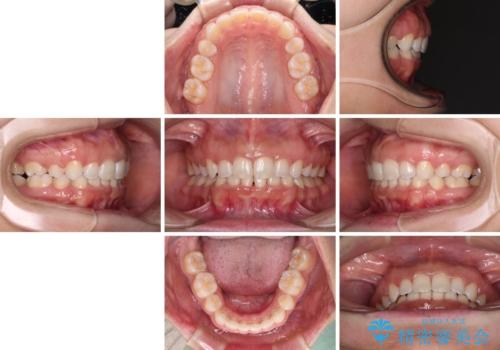

口がしっかりと閉じられない ワイヤー装置での抜歯矯正で出っ歯を改善

それでも根気強く通院してくださり、横からの顔貌の印象が大きく改善され、スムーズに口が閉じられるようになりました。

上下顎ともに前突しており、特に上顎は著しい突出感でした。